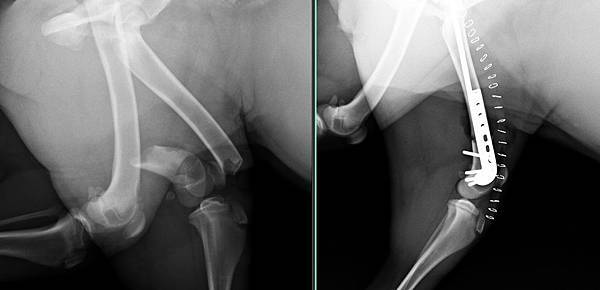

大腿開放性骨折、骨盆脫臼

麗卡被車子壓到

導致大腿開放性骨折、骨盆脫臼

經過醫療團隊努力後

一一修復

很快的在一周內恢復行走能力